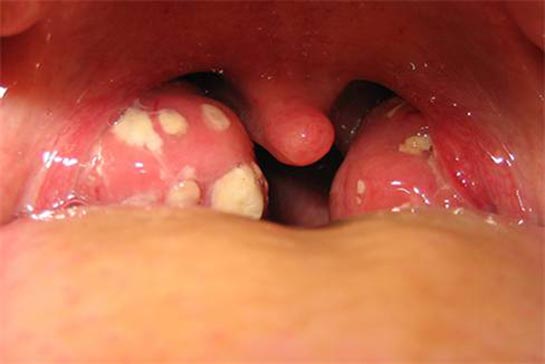

Boğazda Beta Mikrobu Belirtileri ve Tedavisi